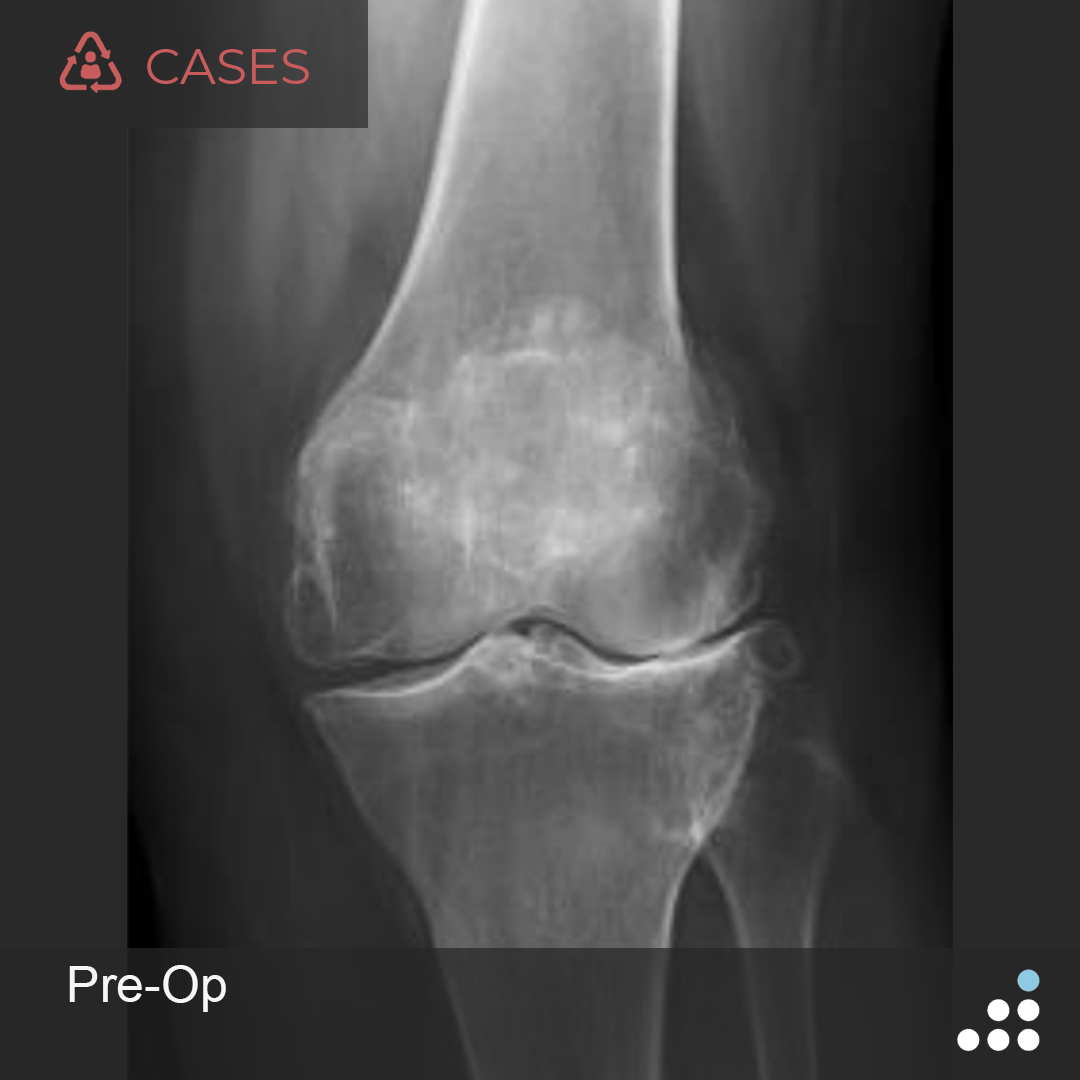

New Case Painful TKA with Recurrent Femoral Component Loosening in 67M Pain Management Orthobullets 2020 california orthopaedic association annual. The patient reports experiencing a dull. The most accurate method to control pain and avoid respiratory depression should include patient controlled analgesia (pca),. Ventura county medical center department of orthopedics. Recommendations are presented regarding pain management, cognitive strategies, physical strategies, strategies for patients on long term. She previously underwent right total knee. Pain Management Orthobullets.